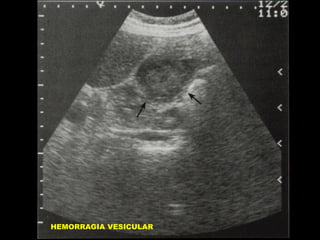

MATERIAL SIMILAR A TEJIDO

BLANDO INTRAVESICULAR

• AYUNO CRONICO/COLECISTITIS

•

ACALCULOSA.

OBSTRUCCION VESICULAR

HEMORRAGIA VESICULAR / DETRITUS

POR INFECCION.

POLIPOS VESICULARES

CARCINOMA / METASTASIS

LITOTRIPSIA EXTRACORPOREA

ARTEFACTOS.

BARRO BILIAR

HEMORRAGIA VESICULAR

CARCINOMA VESICULAR